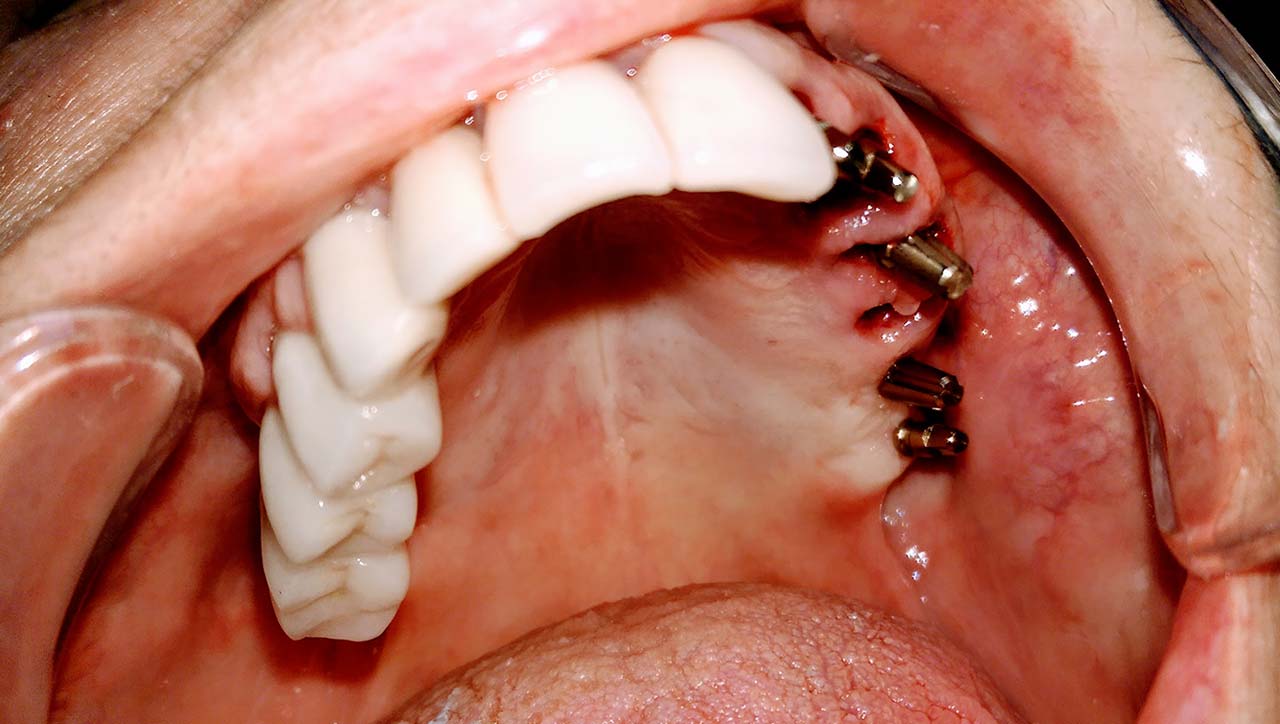

Teljes szájüregi rehabilitáció két lépésben

Ismét egy teljes szájüregi rehabilitáció két lépésben. Először az alsó fogak lettek kihúzva és azonnal implantálva, híddal ellátva, majd később a felső. IHDE svájci azonnal terhelhető implantátumok és cirkónium hidak. Dr. Kelemen Péter és a Symbion Fogtechnika közös munkája.